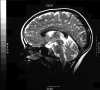

Autosomal recessive spastic ataxia of Charlevoix-Saguenay: a report of MR imaging in 5 patients

We present findings on MR imaging in 5 patients with autosomal recessive spastic ataxia of Charlevoix-Saguenay (ARSACS). In the literature, early atrophy of the superior vermis as well as progressive atrophy of the cerebellar hemispheres and cervical cord was described. We found linear hypointensity on T2 and T2 fluid-attenuated inversion recovery-weighted images in the pons in all of our 5 patients.